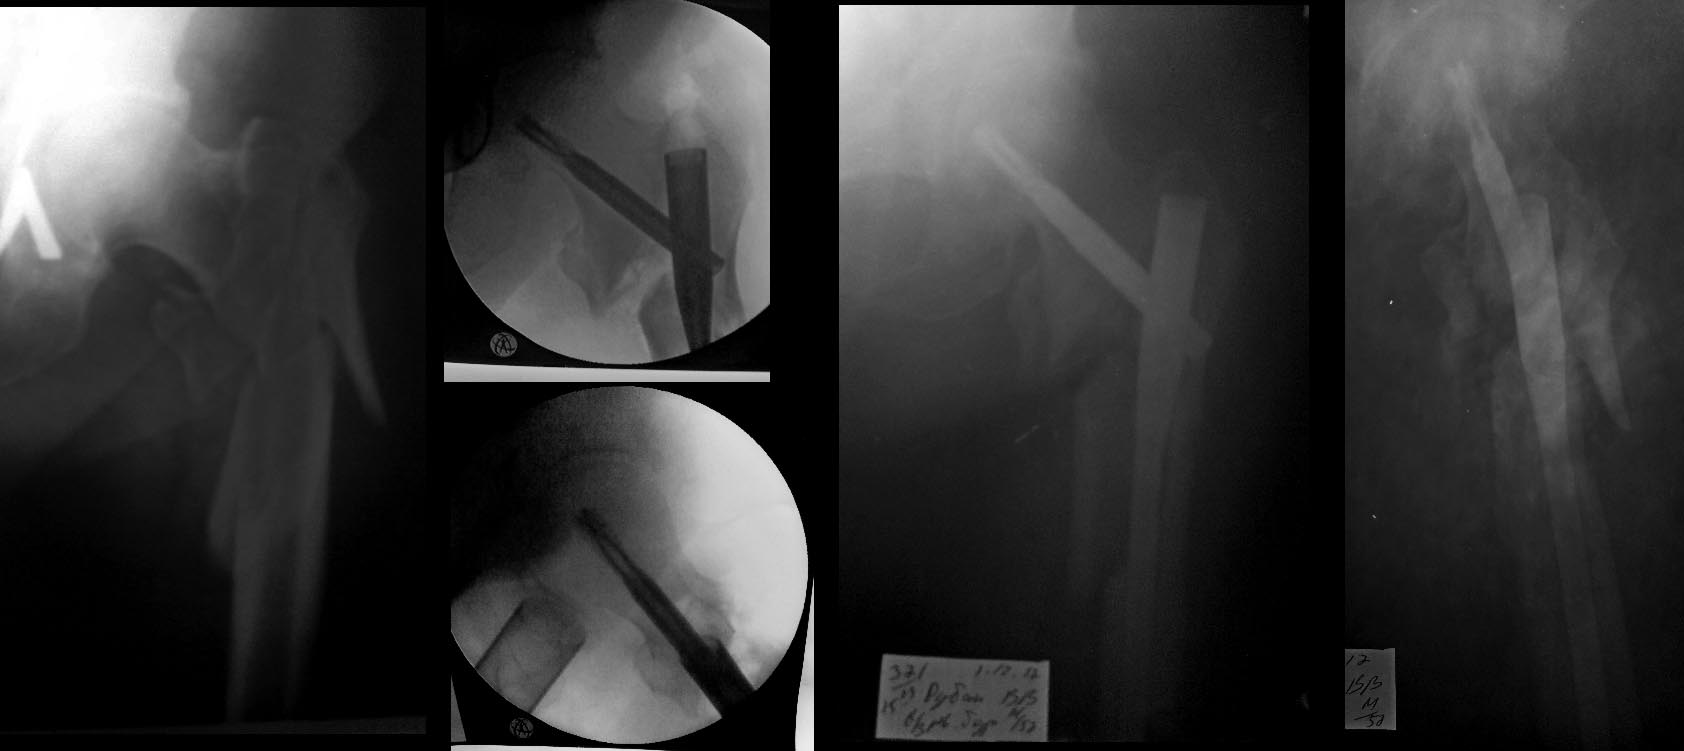

При ресинтезе основание шеечного винта фиксировало латеральную стенку периферического отломка,гвоздь был заперт динамически и телескопирование произошло до определенного уровня.(Rо-3 августа). Возможно,в данном случае, стоило бы больше расточить овальное отверстие.

А что было на дистальном конце стержня? Там оставалось место для дальнейшей динамизации?